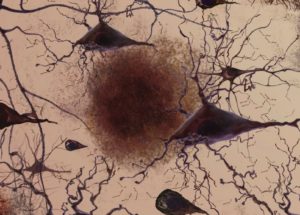

Scientists from the School of Medicine of the University of New York, in the USA, have discovered a hitherto unknown organ, the Interstitium. According to the study, the connective tissue beneath the surface of the skin that lines the digestive tract,…